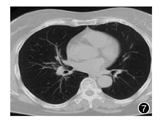

入院诊断:肺结节病。诊治经过:入院后完善支气管镜检查(图3, 图2, 图5, 图6),给予氨溴索化痰治疗并给予泼尼松30 mg 1次/d口服治疗3周,每3周减少10 mg,直至维持量10 mg 1次/d,总疗程6个月。2013年8月30日入院复查,患者咳嗽、咳痰症状完全消失,胸部CT(图7)示双肺透亮度较图1明显增加,右肺门正常;支气管成簇团片样影消失;双侧胸膜下小血管周围微小结节灶消失;复查支气管镜(图8, 图9, 图10, 图11)示双侧支气管黏膜肉芽肿性隆起消失。随访至今未再复发。

本例病例以咳嗽、咳痰为主要症状就诊;胸部CT平扫可见胸膜下小血管周围的微小结节灶、支气管周围成簇团片灶及星云征;支气管黏膜病理提示为慢性肉芽肿性病变,除外其他疾病后诊断为肺结节病。虽经治疗后患者症状完全消失、复查胸部CT平扫肺部病灶消散,但回顾患者就诊历程,对于我们临床医师的启示为:(1)不能只专注于本专业的症状,本专业之外的症状往往具有重要参考价值,如本例患者入院前即有关节肿痛及皮疹,如在皮疹发生时行皮肤组织病理检查及胸片检查可缩短患者确诊时间。(2)对于患者是否需要药物干预,应个体化选择,不能以一般情况替代特殊情况。